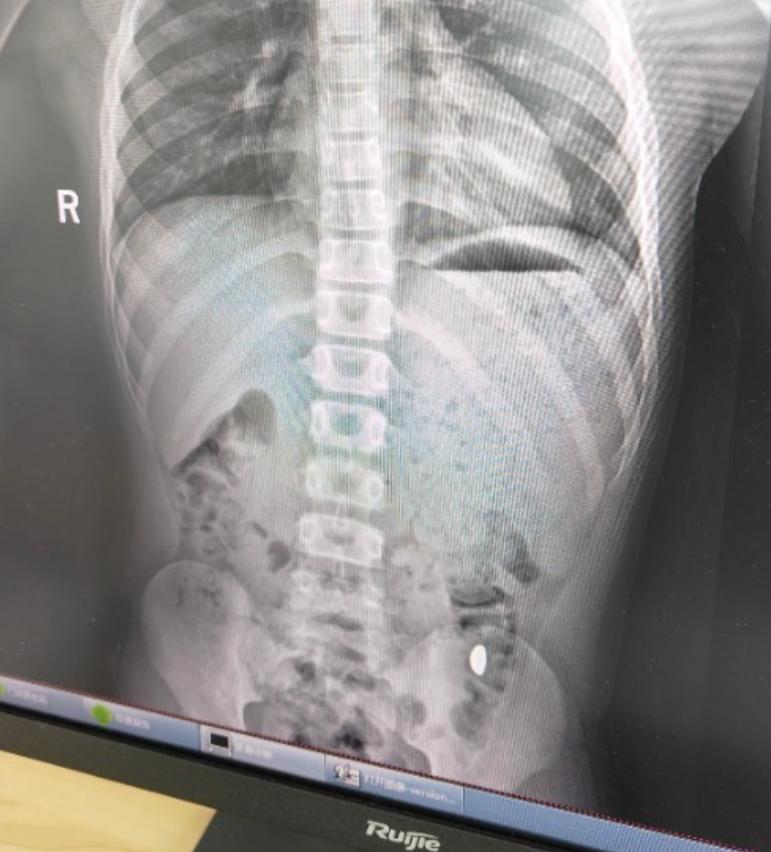

崑山市第五人民醫院門診病歷單顯示,患兒5天前誤吞約10克黃金,其間解兩次大便未發現,目前無腹痛、嘔吐等症狀,診斷結果顯示胃內有異物。

右下加亮點爲金豆。